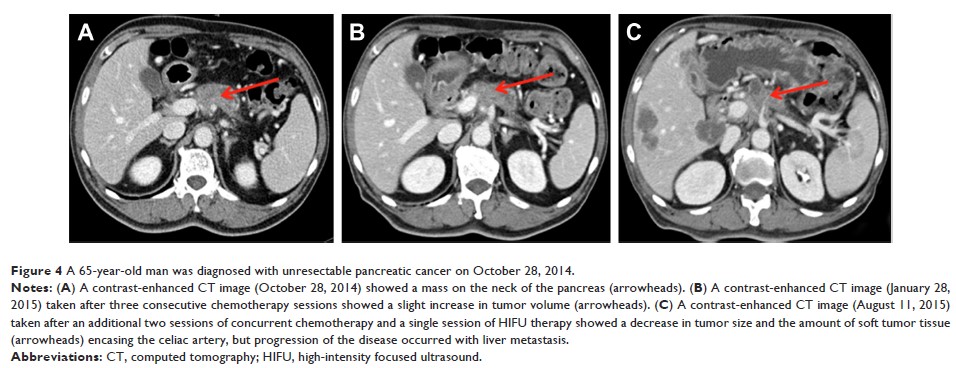

- 作者:Zhouyu Ning, Jing Xie, Qiwen Chen, Chenyue Zhang, Litao Xu, Libin Song, Zhiqiang Meng